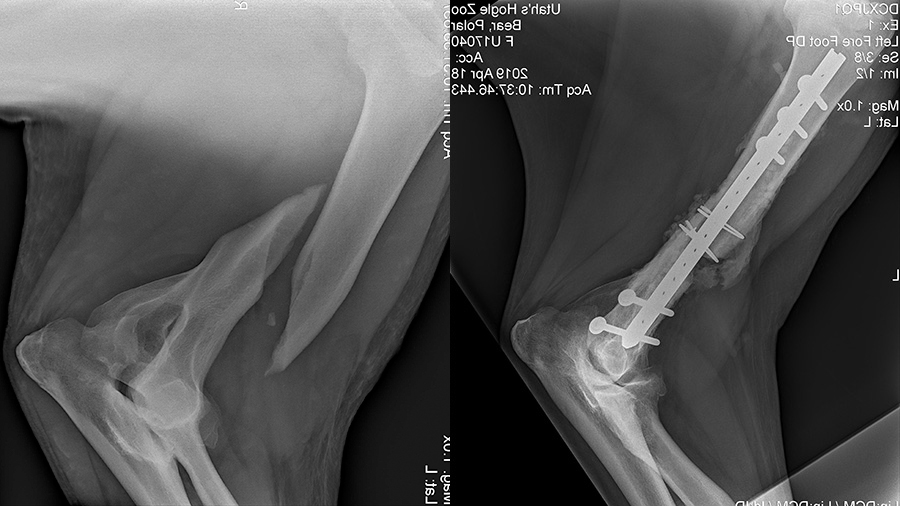

In late January 2019, the 500-pound patient was not moving around normally in her exhibit, unwilling to place weight on her right forelimb. A couple of days after she began showing lameness, Nora’s keepers were able to coax her into a holding area where she could be examined. Radiographs confirmed that her right humerus—the long bone in the forelimb that runs from the shoulder to the elbow—was broken, making it difficult for her to walk. And the fracture wasn’t Nora’s first brush with adversity; she had been abandoned by her mother at birth and, in addition, had been diagnosed with metabolic bone disease as a cub. Her life has been chronicled in social media, and she has captured the hearts of millions, becoming a bona fide Youtube celebrity. One video featuring her has had nearly 13 million views.

“On top of that, we weren’t sure if the intramedullary, interlocking nail, a custom fabricated implant that we developed here at Texas A&M for use in foal humeral factures, would be of sufficient strength to repair a humerus fracture in a 500 pound polar bear and if there was enough room in Nora’s humerus for the implant,” Watkins added.

The surgery took a little over five hours, primarily because of the severe overriding of the fracture, complicating the process of bringing the fractured bone ends into apposition and getting the bone back into its normal alignment.

“We basically had to figure out polar bear anatomy as we approached the bone. Once we had exposed the humerus it took quite a bit of time to get the fracture reduced. This was due to the marked overriding of the fractured ends and the fact that the powerful muscles in Nora’s limb were contracted—all of which we had to overcome to return the fractured ends to their normal position and realign the humerus,” Watkins recalled. “Once the fracture was aligned, fixation with the interlocking nail was fairly straight-forward, but with the density of her bone, it was more difficult than typically encountered when repairing a foal’s humerus.”